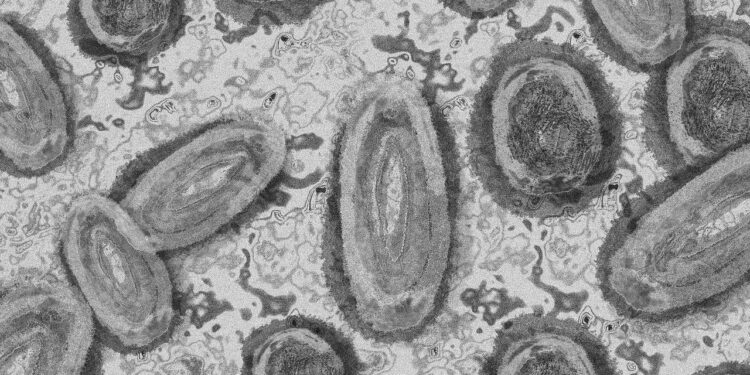

La Secretaría de Salud de México informó que hasta el momento se han confirmado 49 casos de mpox en 11 estados del país. Sin embargo, aclaró que no se han registrado casos de la nueva variante clado 1b, que ha llevado a la Organización Mundial de la Salud (OMS) a declarar una emergencia sanitaria internacional.

Entre el 1 de enero y el 3 de agosto, se reportaron 212 casos probables de mpox en México, de los cuales 49 han sido confirmados. Las autoridades sanitarias han identificado únicamente casos de la variante clado II en el país, mientras que la variante clado I, que circula en África, está asociada con una transmisión sostenida y afecta a personas de diversas edades, incluyendo menores de 15 años.

La Secretaría de Salud detalló que la mpox cursa con dos fases clínicas: la primera, que se desarrolla en los primeros cinco días, incluye fiebre, dolor de cabeza intenso, ganglios inflamados, dolor de espalda baja, dolores musculares y falta de energía. La segunda fase se caracteriza por la aparición de ampollas y un sarpullido que comienza en la cara y se extiende al resto del cuerpo.